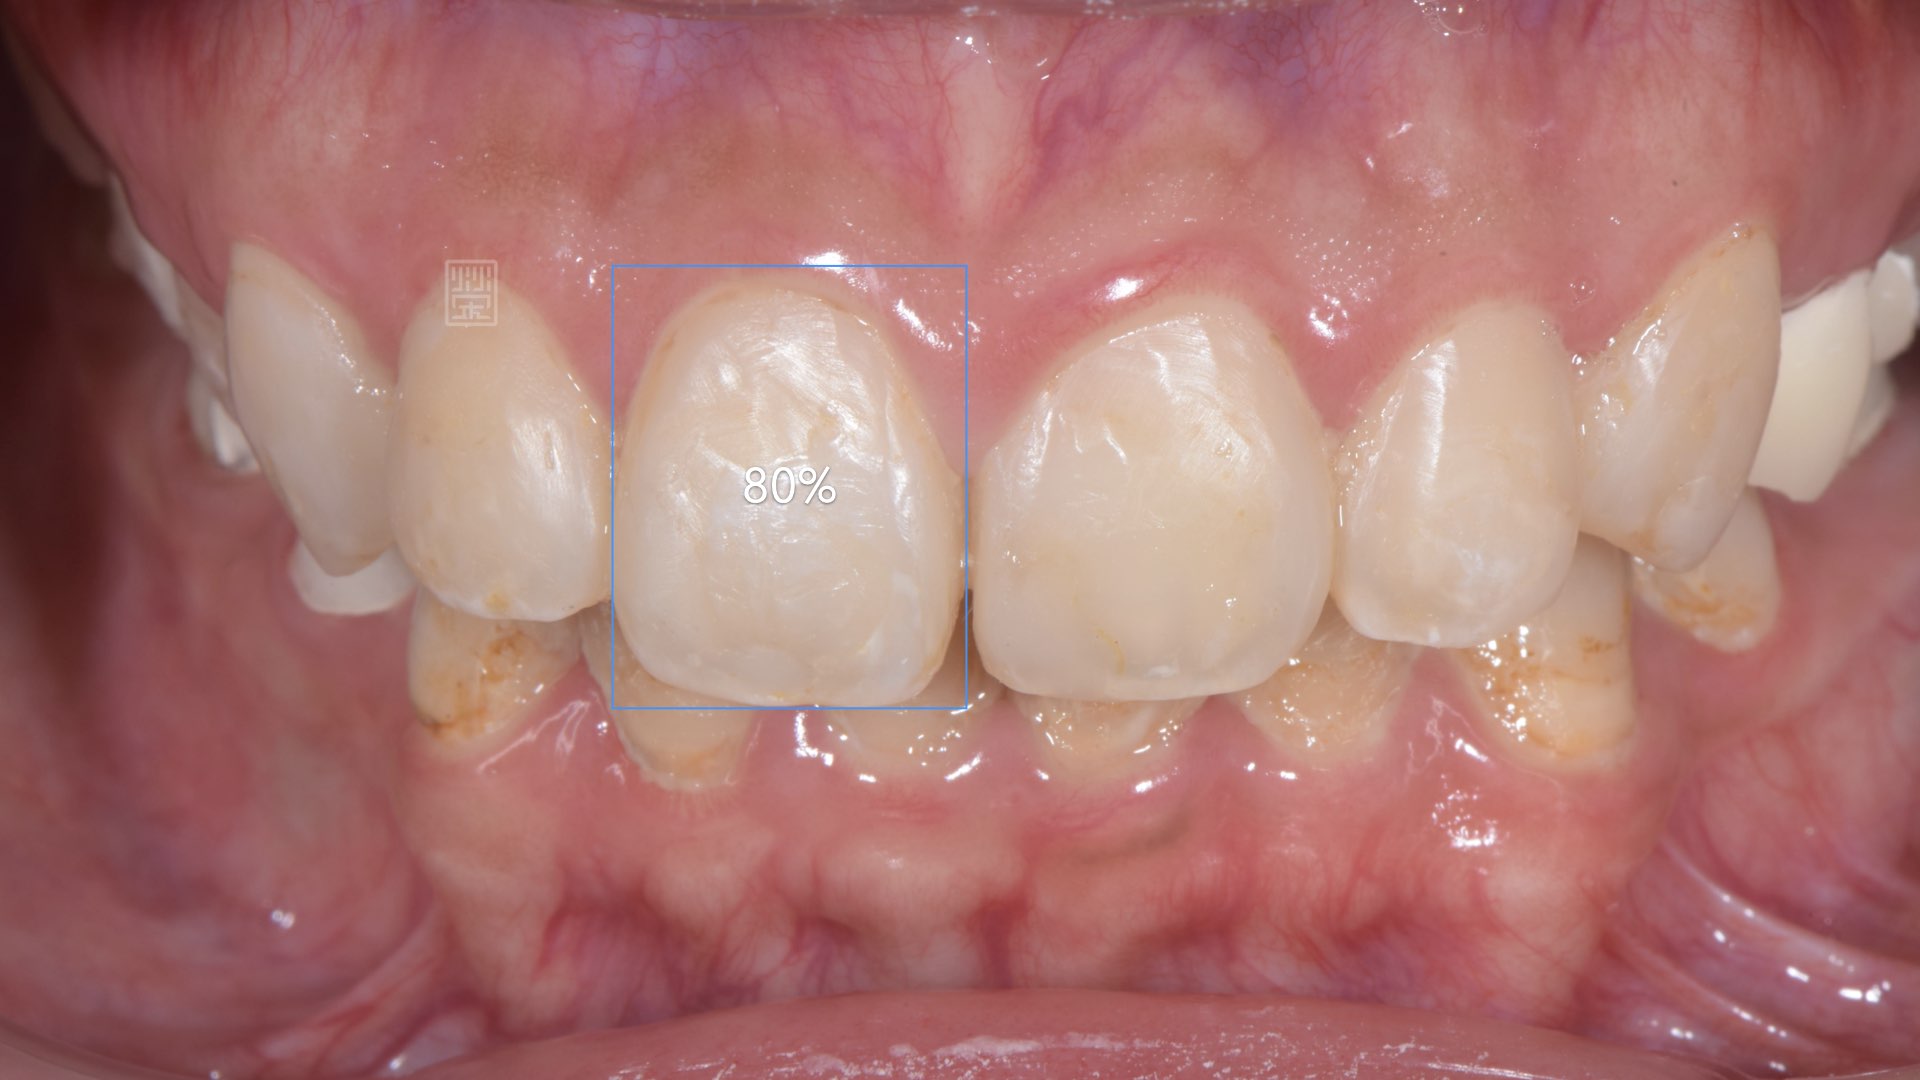

重新樹脂填補完畢

重新樹脂填補完畢,門齒比例80%,不宜做牙冠增常術